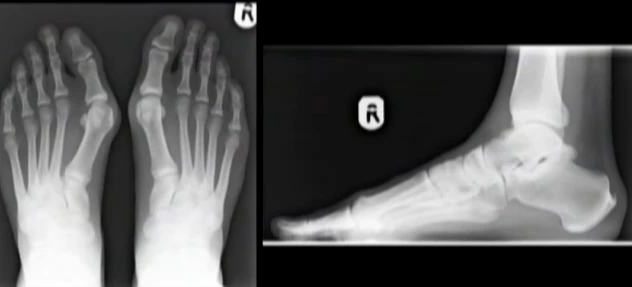

Hình ảnh chụp X-quang xương bàn chân bị tổn thương do đi giày cao gót.

Với sự trợ giúp của máy quét, các chuyên gia tại bệnh viện đã có thể thấy rằng mang chiếc giày cao gót buộc bàn bàn chân phải ép vào một hình dạng không tự nhiên.

Điều này sẽ khiến bàn chân bị đau và tổn thương kéo dài, đặc biệt nếu thường xuyên sử dụng giày cao gót.

Đi giày cao gót khiến đôi chân bạn không được tự do, xương bàn chân bị ép theo khuôn dẫn đến dễ bị dị dạng.

Từ những minh họa 3D này, các chuyên gia đều khuyến cáo phụ nữ chỉ nên đi những đôi giày cao gót vừa phải.